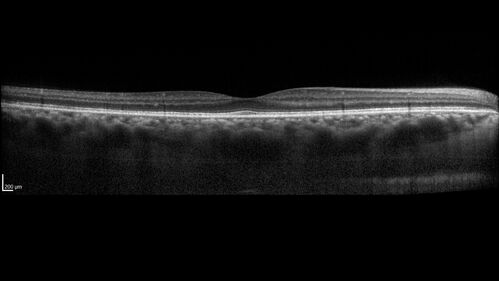

Ocular Lymphoma - Initially presented like auto-immune retinopathy

43 year old man: initial presentation - The vision in the left eye is blurry and opaque for about 2 weeks.  In the central of the vision, when he covers the right eye, in the center of the left eye there is a film with a light in the middle.  This has never happened before.  He has not been sick for the last few months.  A few weeks ago he saw waves on the floor when looking down but that has gone away.  Since the vision loss started the vision has not changed much.  The central vision is not getting better.

VA improved over 2 months to normal.  Then the patient had 2 more episodes of self-limited vision loss (no treatment).  Then 2 years later he presented with a diagnosis of CNS lymphoma and later developed subretinal deposits (last images)